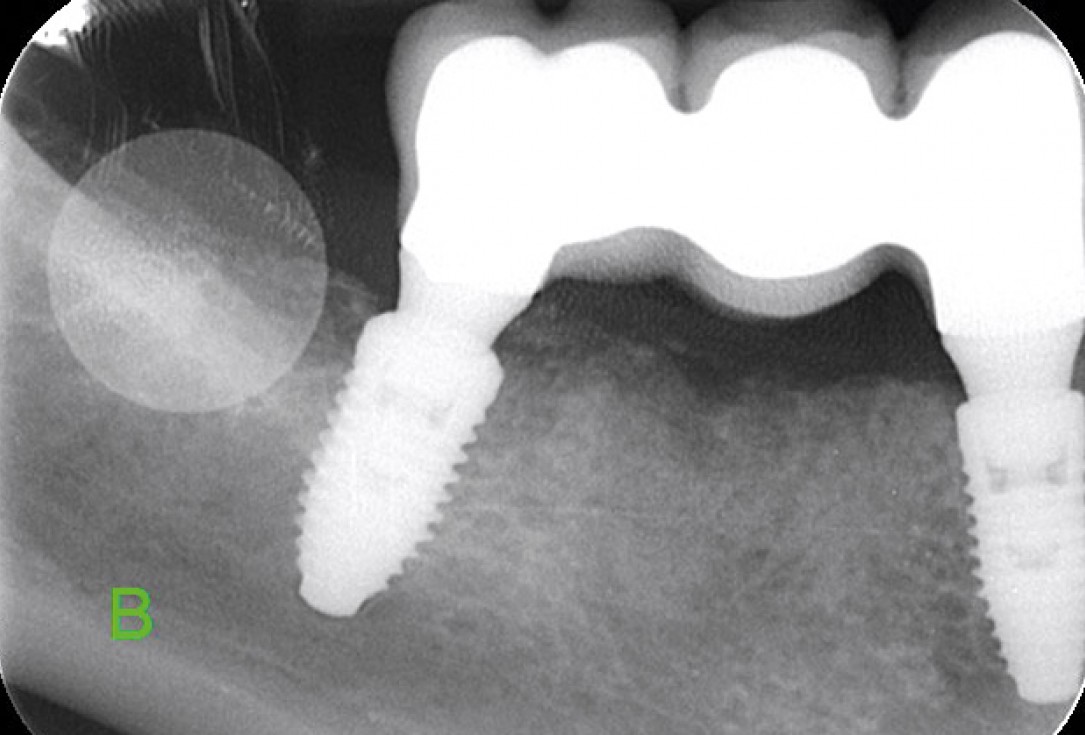

Multiple socket preservation in the mandibular with collacone® max – Dr. D. Jelušić